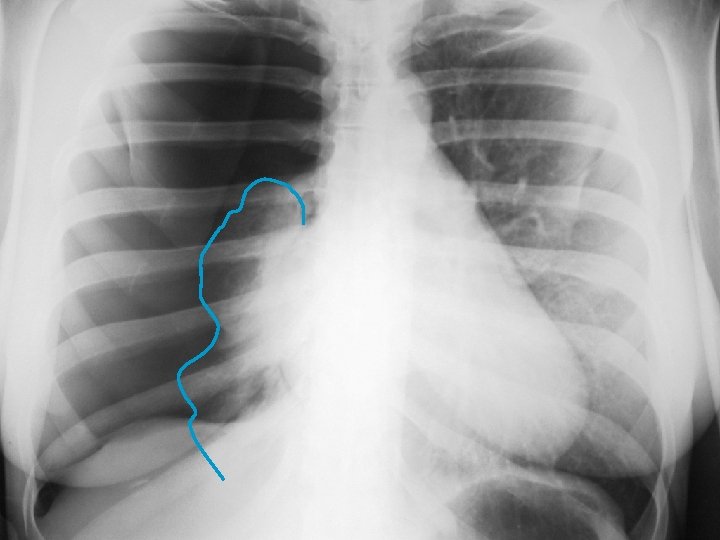

PNT spontanée du sujet jeune Le pneumothorax est lié à la rupture de bulles d’air sous -pleurales. CDD : douleur thoracique brutale spontanée ou lors d’un effort. Parfois dyspnée Examen : tympanisme hémithoracique. Recherche de signes de détresse respiratoire (polypnée, cyanose, sueur, tirage…) Radio : hyperclarté périphérique séparée du poumon par le « liséré capillaire » : image de la plèvre viscérale. La radio fait le diagnostic

Exsuflation à l’aiguille